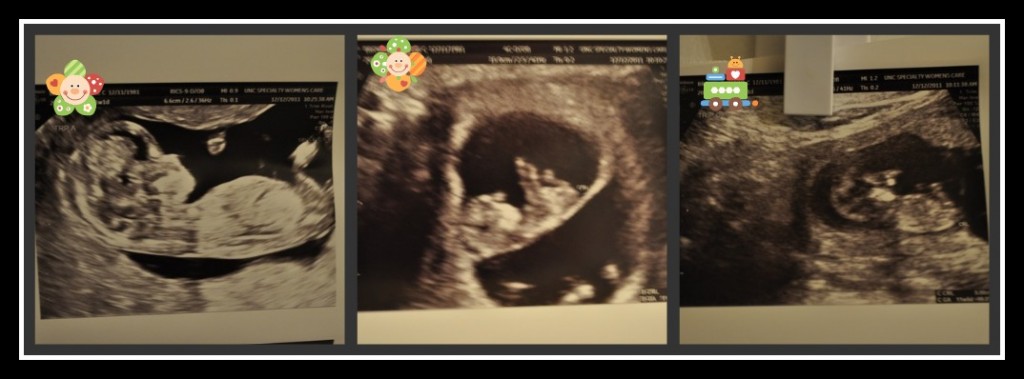

I’ve been meaning to post about our high-res/NT scan ultrasound from last Monday. But a crazy busy week got in my way. To summarize: Pregnancy brain hit & we were a half hour late {we had genetic counselor appt at 830 & U/S appt at 9, I just remembered the 9a appt time}, so we hung out in the lobby for a while & read a pregnancy magazine cover-to-cover, counselor was nice, ultrasound tech got impatient that babies B & C weren’t cooperating for the NT measurement=pain as she jabbed me, finally got measurements from A & C, all was better once we saw doctor who assured us babies looked awesome.

I received a call midweek saying our babies chances for trisomy 13 & 18 were less than 1/10,000 & for Down’s less than 1/3382. So we’re happy.